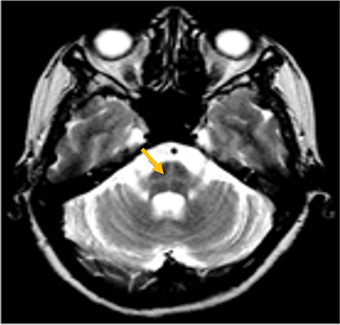

다계통 위축이란 뇌의 다양한 계통에서 위축이 발생하는 것을 의미합니다. 파킨슨 증상이 있으면서 질병 초기에 소변 장애나 기립성 저혈압으로 인한 어지러움이 두드러지게 나타나는 경우, 보행 시 비틀거림이나 구음 장애와 같은 소뇌 위축에 따른 운동 실조 증상이 나타나는 경우, 꿈에서 하는 행동을 수면 중에 보이는 렘수면 행동 장애가 동반되는 경우 다계통 위축을 의심합니다. 다계통 위축은 파킨슨병과 달리 안정 시 떨림이 잘 보이지 않고, 증상이 대칭적인 경우가 많으며, 진행이 빠르며, 레보도파와 같은 항파킨슨 약제에 잘 반응하지 않습니다. 다계통 위축은 뇌 자기공명영상(MRI)에서 교뇌에 십자 모양의 고음영이 나타날 수 있는데, 이를 십자무늬 빵(hot cross bun) 징후라고 합니다. 또한 초기에서는 뇌 자기공명영상(MRI)이 정상으로 보이더라도 뇌포도당 양전자 단층촬영(PET)에서는 소뇌 또는 기저핵의 대사 기능이 저하된 상태가 관찰될 수 있습니다. 이러한 영상 소견은 특징적인 임상 증상과 함께 진단에 참고할 수 있습니다.

[다계통위축 환자의 뇌자기공명영상에서 확인되는 십자무늬빵 징후]